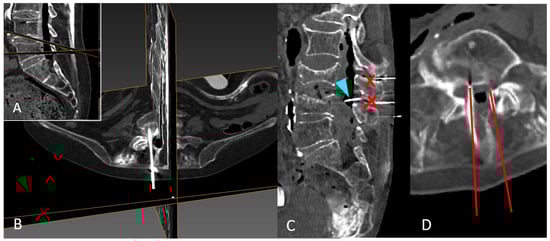

2.5. CT and 3D Reconstruction

2.6. Anatomical Illustration of Needle Path and Affected Structures